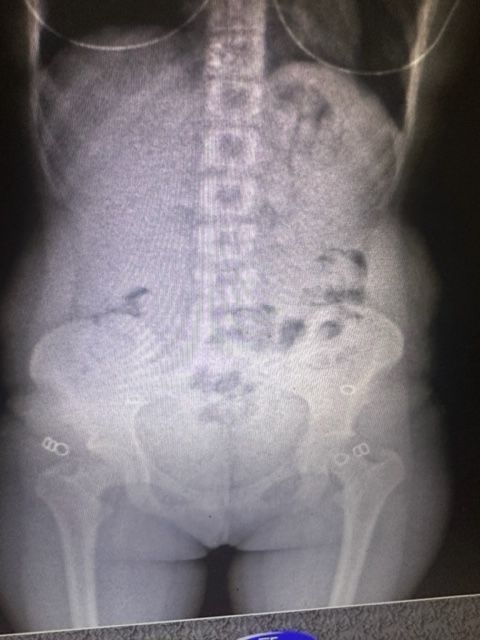

En la primera revisión del equipaje de las mujeres no se encontraron resultados positivos, sin embargo, con la autorización del Juzgado Nacional en lo Penal Económico N°7, una requisa personal, junto con un body scan descubrieron la presencia de estupefacientes.

Así, las pasajeras fueron trasladadas al hospital interzonal de Ezeiza, detenidas e incomunicadas, donde, al cabo de su internación, se constató que una de ellas llevaba nada menos que 946 gramos de cocaína en su organismo y la otra, 823 gramos.

Así, el total de la droga encontrada asciende a 1.769 gramos. En los términos establecidos por el artículo 866 del Código Aduanero, las mujeres podrían enfrentar penas de hasta 12 años de prisión, cada una.